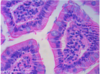

Sublingual Gland

* Mucous acini (pale in appearance)(PAS+)

* Flattened nuclei at basal poles of cells.

* Myoepithelial cells surround acini.